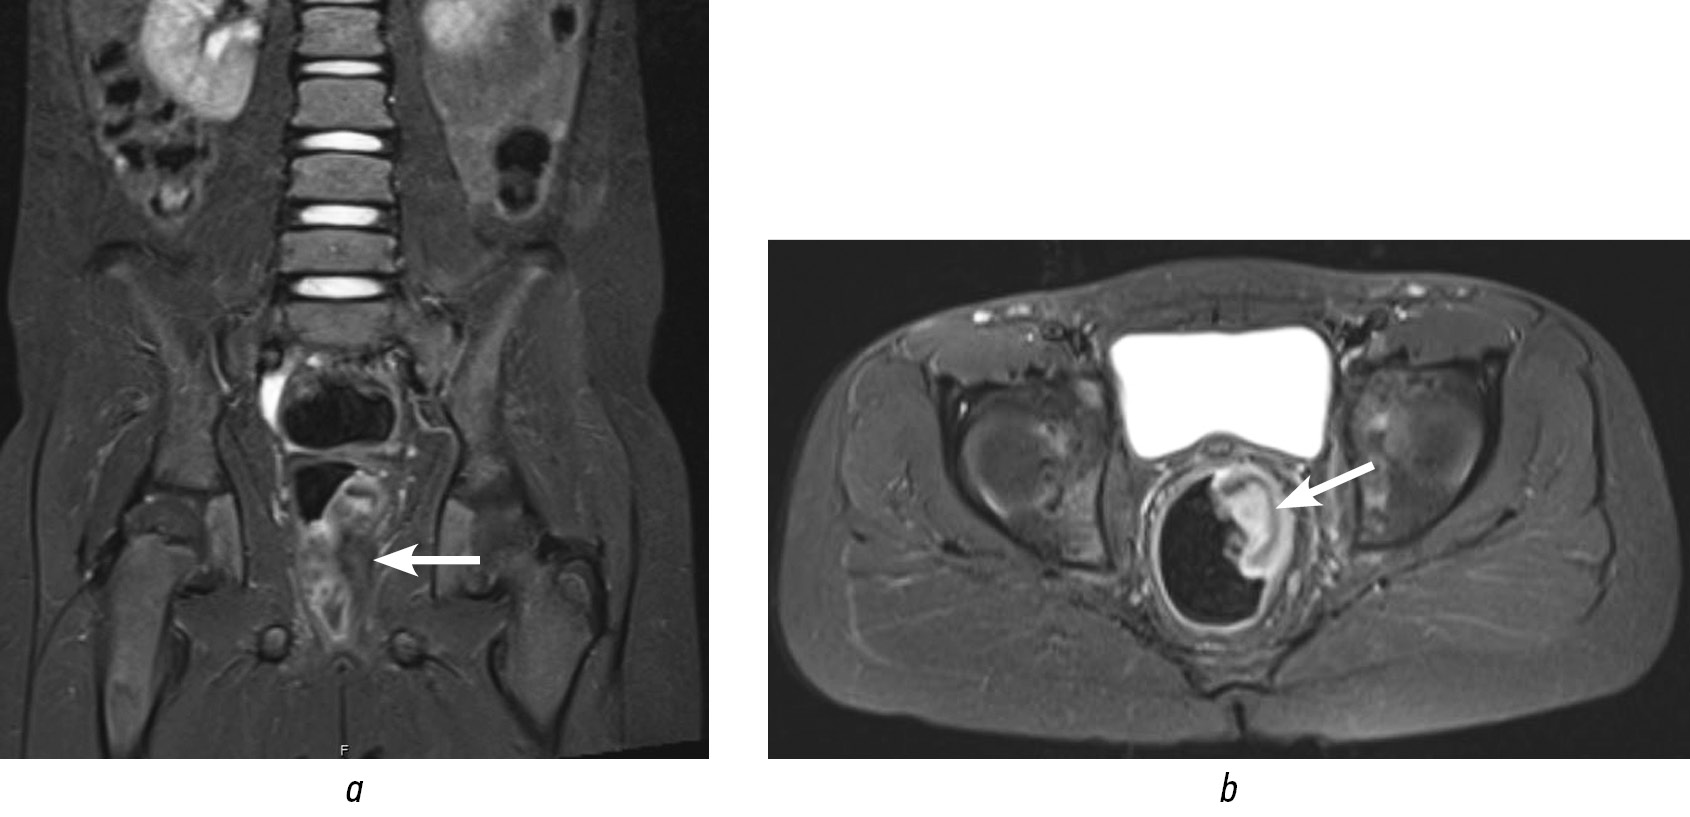

Тактика обсуждена с онкологами, решено выполнить ревизию под наркозом и расширенную открытую биопсию опухолевидного образования прямой кишки (рис. 2).

Рис. 2. Осмотр анального канала под наркозом. Визуализация опухолевидного образования прямой кишки по передней стенке (указано стрелкой).

Fig. 2. Examination of the anal canal under anesthesia. Tumor-like mass of the rectum visualized on the anterior wall (indicated by an arrow).